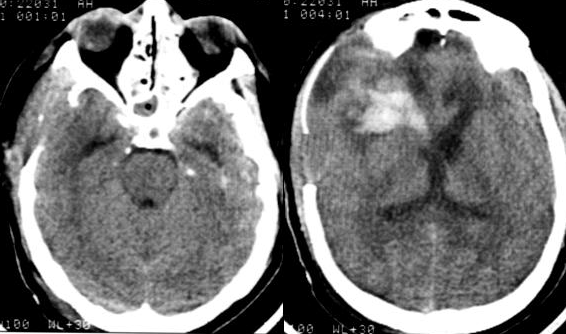

На третьи сутки после операции была отмечена положительная динамика: кома I, частичный регресс левостороннего гемипареза. При проведении КТ-исследования головного мозга выявлены признаки санации ликвора в виде снижения плотности крови в желудочковой системе, уменьшение размеров гематомы правой лобной области. Базальные цистерны прослеживались более четко, зон пониженной плотности вещества мозга выявлено не было (Рис. №4).

Продолжалась ИВЛ в режиме SIMV. Гемодинамически больная была стабильна уже без вазопрессорной поддержки. Инвазивный мониторинг гемодинамики прекращен. Эпизодов полиурии не было. Концентрация натрия в плазме стабилизировалась на уровне 149-151 ммоль/л. Удельный вес мочи составил 1010-1012. Показаний к применению десмопрессина не было.

В период 3-7 суток отмечалась положительная динамика неврологического статуса в виде восстановления сознания и дальнейшего регресса левостороннего гемипареза. По данным ТКДГ выявлено снижение линейной скорости кровотока (Табл. №2).